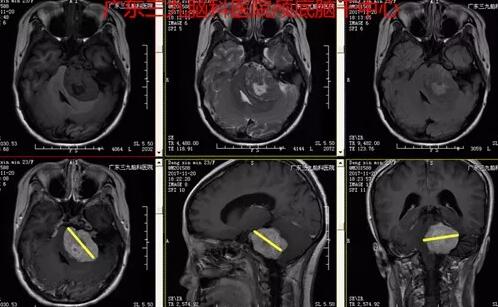

图3:2017-11-20 头颅MR示左侧桥小脑角区一团块状稍长T1等T2为主异常信号影,FLAIR呈偏等信号,增强扫描不均匀明显强化,病灶大小约117.5px×87.5px×90px,边缘示增宽的蛛网膜下腔,左侧内听道明显扩大,左侧听神经颅内段明显增粗,邻近脑干、左侧桥臂、左侧小脑半球受压。右侧听神经颅内段稍增粗,增强扫描明显强化